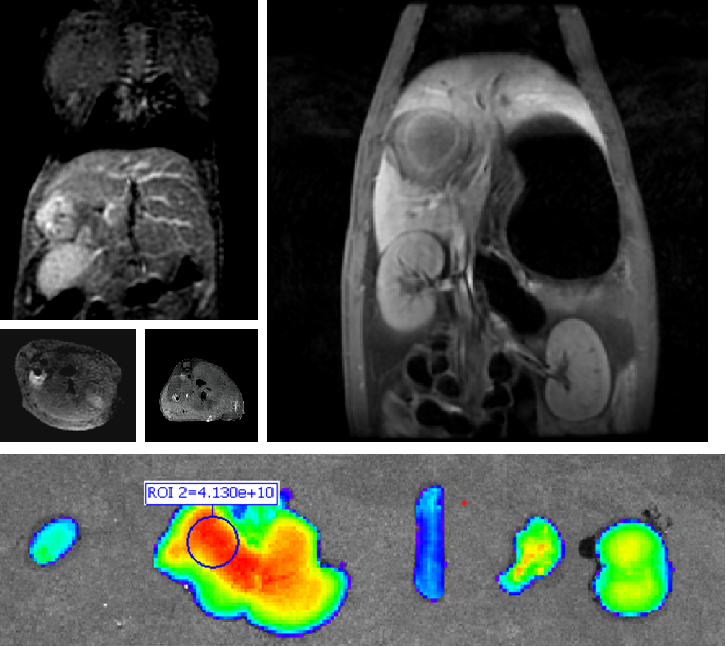

PL002是浙江普利药业有限公司研发的荧光/磁共振双模态造影剂,荧光/磁共振双模态造影剂的成功研发将成为提高脑胶质瘤手术效率的有效方案。术中荧光技术与核磁共振成像的结合,相较于单独使用,能够更准确地识别肿瘤组织与功能区的位置关系,以及患者的肿瘤浸润边缘。

PL002相较于吲哚菁绿具有明显优势。目前吲哚菁绿在临床使用中存在给药到手术时间不确定的问题,可能造成病灶与正常组织对比度不足,影响术中的病灶的判断,PL002采用独特的钆络合物与荧光分子共价键结合的分子结构设计,这种设计能够让医生在术前通过磁共振成像确定造影剂在病灶中的聚集情况,进而针对患者个体情况来对手术时间进行规划。同时,由于PL002体内更为稳定,在荷瘤小鼠模型中同等条件下荧光成像效果维持时间长于现有荧光造影剂,也保证了其在临床应用中具有更宽的手术窗口。

使用双模态造影剂可以为手术医生提供更加丰富的诊断信息,降低术中的决策压力,避免过度切成,增加发现微小病灶的可能性,最终实现患者的全面获益。此外,相较于传统荧光造影剂,PL002的安全性更高、体内更为稳定,成像效果更佳,为其临床使用提供了有效的支持。

2023年10月,PL002获得FDA签发的美国药物临床试验批件,用于原发性肝癌患者的术前诊断及术中导航。2024年11月,PL002获得中国药物临床试验批准,用于脑胶质瘤患者的术前诊断及术中导航。这是普利制药第一张国际和国内造影剂创新药临床批件。普利制药关于PL002在专利保护方面同样进行了布局,目前已有4项中国专利,2项PCT专利获得公开。